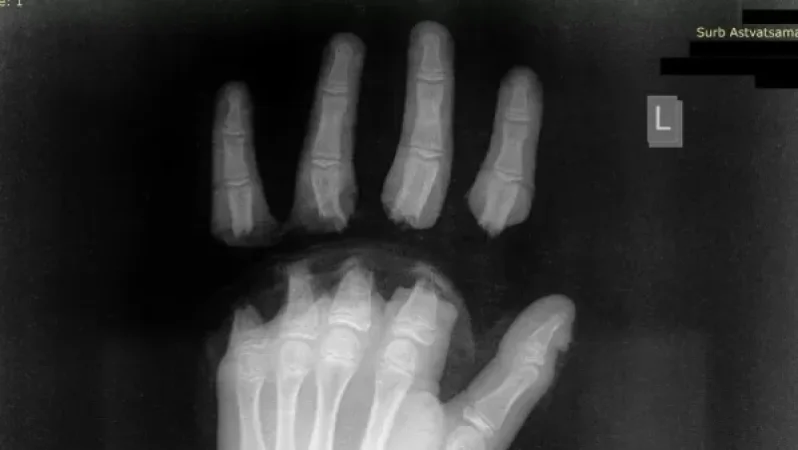

«Սուրբ Աստվածամայր» ԲԿ-ի մամուլի խոսնակ Գևորգ Դերձյանը ֆեյսբուքի իր էջում տեղեկացնում է. ««Սուրբ Աստվածամայր» ԲԿ է ընդունվել 12 տարեկան երեխա՝ ձեռքի չորս մատների ամպուտացմամբ (անդամահատված):

Դեպքը տեղի է ունեցել շան հետ խաղալիս: Կենդանին վզկապի փոխարեն կապված է եղել պողպատե թոկով (տռոս), որի մյուս ծայրը փաթաթված է եղել երեխայի մատներին, վազելու ժամանակ այն ձգվել է, ինչի հետևանքով տղայի չորս մատները կտրվել են:

Երեխան տասը ժամ վիրահատվել է, «Սուրբ Աստվածամայր» ԲԿ-ի պլաստիկ վիրաբույժները կատարել են ձեռքի մատների ռեպլանտացիա: